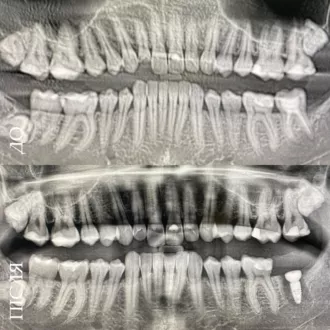

Результат коррекции металлической брекет-системой

Результат коррекции самолигирующей брекет-системой

Результат коррекции элайнерами

Результат коррекции керамической брекет-системой